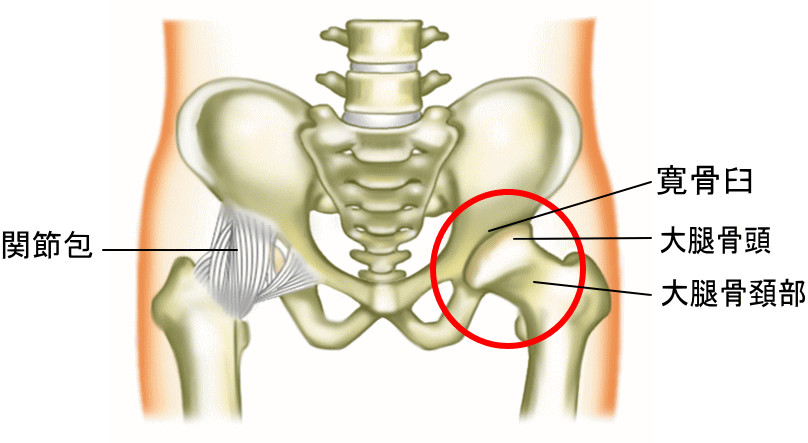

股関節とは 図 (460 無料画像)

股関節の構造股関節のしくみ股関節の痛み関節の痛み人工関節ドットコム。

骨盤・股関節の解剖学 – McDavidサポータ-ブランドのマクダビッド オフィシャルサイト。